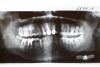

et2000 Опубликовано 25 июня, 2013 Автор Поделиться Опубликовано 25 июня, 2013 (изменено) панорамный снимок (ОПТГ) 25/06/2013 - болит 2011 год не болело Изменено 25 июня, 2013 пользователем et2000 Ссылка на комментарий

IvanK Опубликовано 27 июня, 2013 Поделиться Опубликовано 27 июня, 2013 на снимках нет полноценного контактного пункта между 38-37.Советую:Проф.гигиена + обучение гигиене (обязательно пользоваться зубной нитью)Консультация ортодонта, ортопеда, пародонтологаСкорее всего придется удалить 8-киКоронку на 47 нужно поменять..Больше можно сказать только на очной консультации Ссылка на комментарий